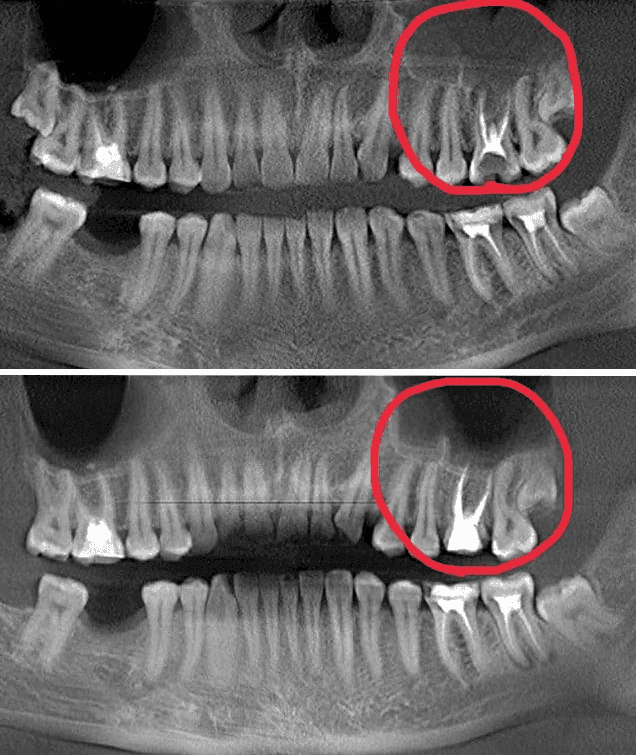

Пациент обратился с острой болью от зуба, жалобам на односторонний гайморит , боли при жевании

Провели эндодонтическое лечение под микроскопом, распломбировали корневые каналы, нашли дополнительный (который и являлся источником инфекции)

Ушли болевые симптомы и гайморит, зуб спасен, пациент здоров